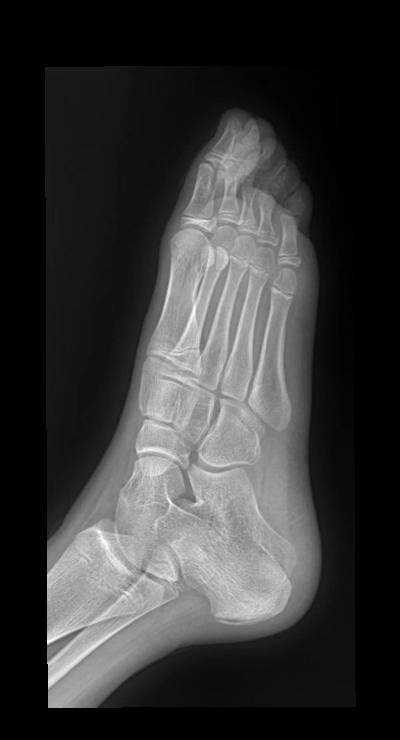

足外伤 14岁 女 第一跖骨软组织肿胀